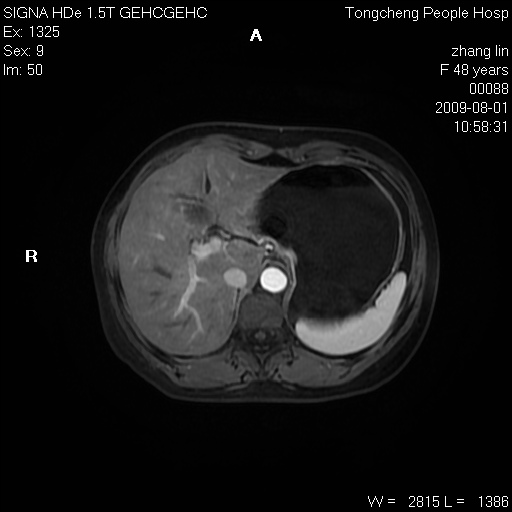

女,48岁。健康体检,彩超发现右肾占位性病变。平素健康。

临床诊断:右肾占位性病变,性质待定(囊肿?肿瘤?)。

上中腹部mr平扫+增强扫描,图像如下:

右肾上极见一类圆形病灶,t1wi呈等信号t2wi呈等高混杂信号,三期增强无强化,边界清---考虑囊肿出血。

同反相位均表现为等信号,病变无强化,考虑含蛋白的囊肿可能,弥散加权相或许有些帮助,

肝囊肿